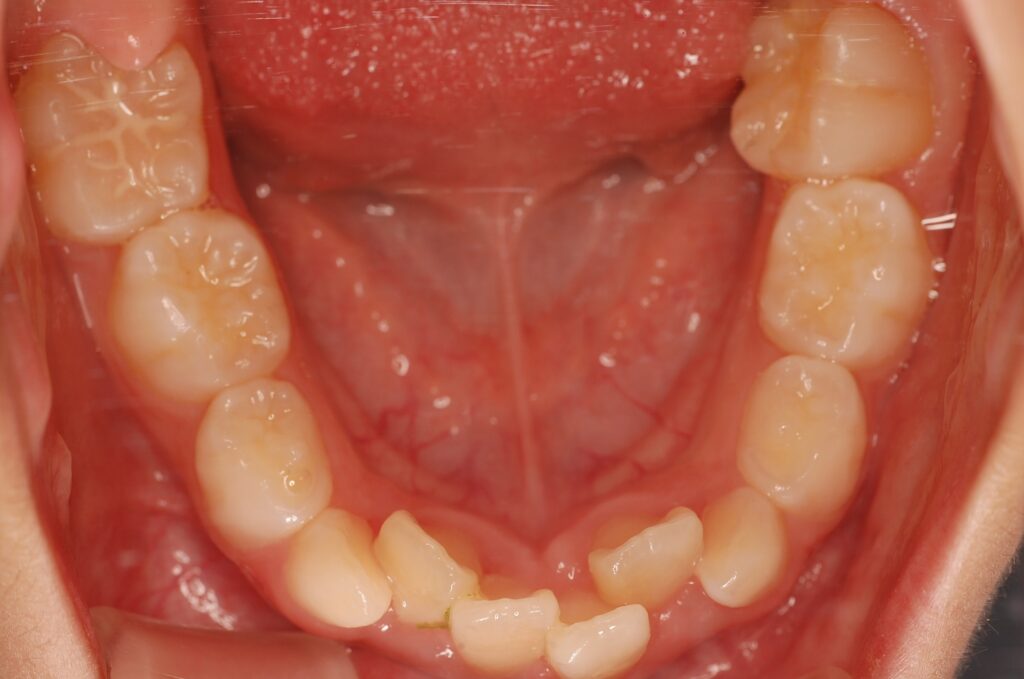

こちらの症例は、向かって右側の一番奥の歯が内側に倒れこんでいるのがわかると思います。

このように、噛み合わせの面が真上から良く見えないようなケースを傾斜といいます。

その中でも舌側に倒れこんでいるものを「舌側傾斜」と呼びます。